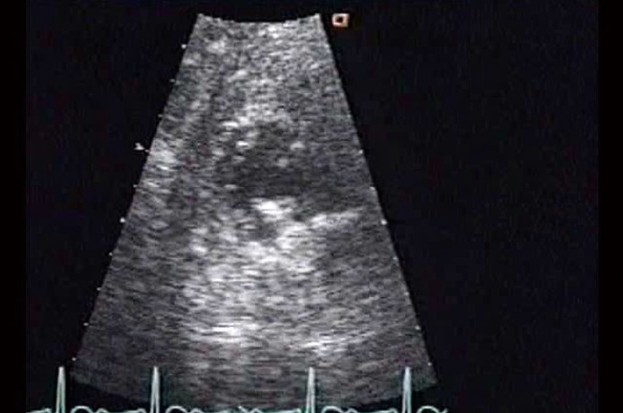

発熱後に多発性脳梗塞を生じた症例である.心エコー断層像では,輝度の高い径12×10mmの可動性腫瘤が僧帽弁輪(後尖側)に付着している(図A~C黄矢印).弁輪自体が石灰化しており,可動性腫瘤も輝度が高い.一方で,弁尖自体は大きな変化はなく,僧帽弁逆流も軽度で,ドプラ上も僧帽弁狭窄の所見はみられない.以上より,②「僧帽弁後尖の逸脱がみられる」,③「僧帽弁前尖に可動性構造物が付着している」,⑤「僧帽弁狭窄がみられる」は誤りで,①「僧帽弁輪石灰化がみられる」,④「僧帽弁輪に可動性構造物が付着している」は正しい.

(左から) 図A 胸骨左縁長軸像, 図B 胸骨左縁短軸像, 図C 心尖部四腔像[画像はクリックで拡大]

図A~Cともに可能性腫瘤を認める(黄矢印).